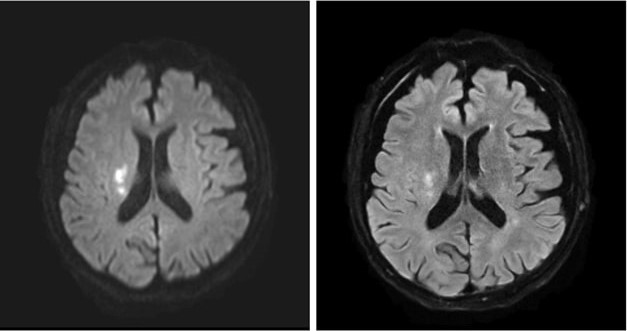

Why Ultrafast MRI Is the Future of Acute Stroke Triage

Lang et al. make their case for choosing MRI over CT for initial acute infarct screening.